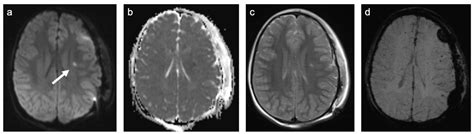

The white matter is comprised of axons—long nerve fibers—insulated by a substance called myelin. Myelin is what gives white matter its color, and its primary function is to speed up electrical impulses. In Cerebral White Matter Disease, the myelin sheath becomes damaged, or the small blood vessels supplying these areas become compromised. This damage is most commonly visible on MRI scans as bright, white patches, hence the term white matter hyperintensities.

Diagnosis is primarily achieved through neuroimaging. An MRI of the brain is the gold standard for identifying these lesions. Radiologists often use scales like the Fazekas scale to quantify the severity of the damage. In addition to imaging, doctors will perform a comprehensive medical evaluation to rule out other neurological conditions that might mimic the symptoms of Cerebral White Matter Disease.

• MRI Brain Scan: Using T2-weighted or FLAIR sequences to clearly visualize hyperintensities.